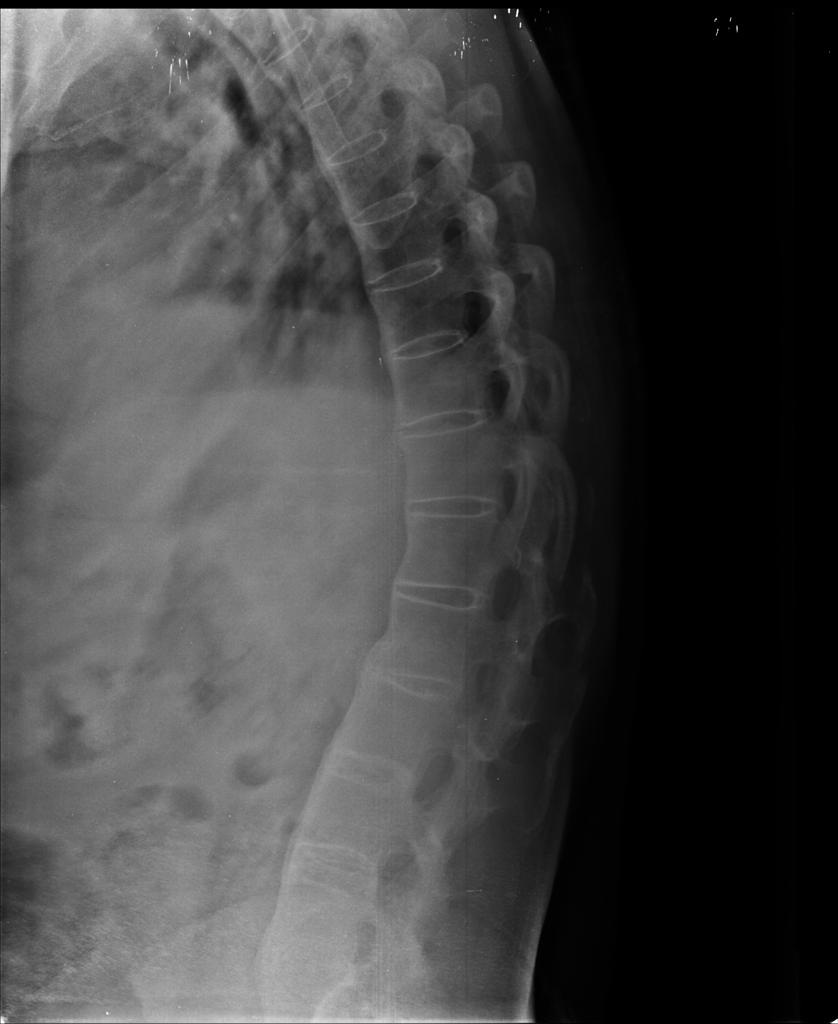

Bamboo spine appearance in the thoracolumbar graphy (shown by the arrow Medical Definition For Bamboo Spine ankylosing spondylitis (as) is a type of arthritis that affects the joints in your spine. ankylosing spondylitis (as) is a chronic form of inflammatory arthritis that primarily affects the spine, causing back pain and stiffness. A complication of ankylosing spondylitis, bamboo spine involves fused. in today’s blog, we take a closer look at bamboo spine and your. Medical Definition For Bamboo Spine.

Bamboo spine appearance on plain radiograph and MRI showing gross Medical Definition For Bamboo Spine It gives the spine a very symmetrical and segmented appearance. ankylosing spondylitis is the prototypical spondyloarthropathy and a systemic disorder characterized by inflammation of the axial. the meaning of bamboo spine is a spinal column in the advanced stage of ankylosing spondylitis especially as observed in an x. bamboo spine is a term that refers to a. Medical Definition For Bamboo Spine.

Characteristic " bamboo " spine. Download Scientific Diagram Medical Definition For Bamboo Spine in today’s blog, we take a closer look at bamboo spine and your treatment options for severe cases of ankylosing spondylitis. ankylosing spondylitis (as) is an inflammatory disease that affects the joints and bones of the spine. in its advanced stages, ankylosing spondylitis (as) can lead to a condition that is sometimes called bamboo spine. ankylosing. Medical Definition For Bamboo Spine.